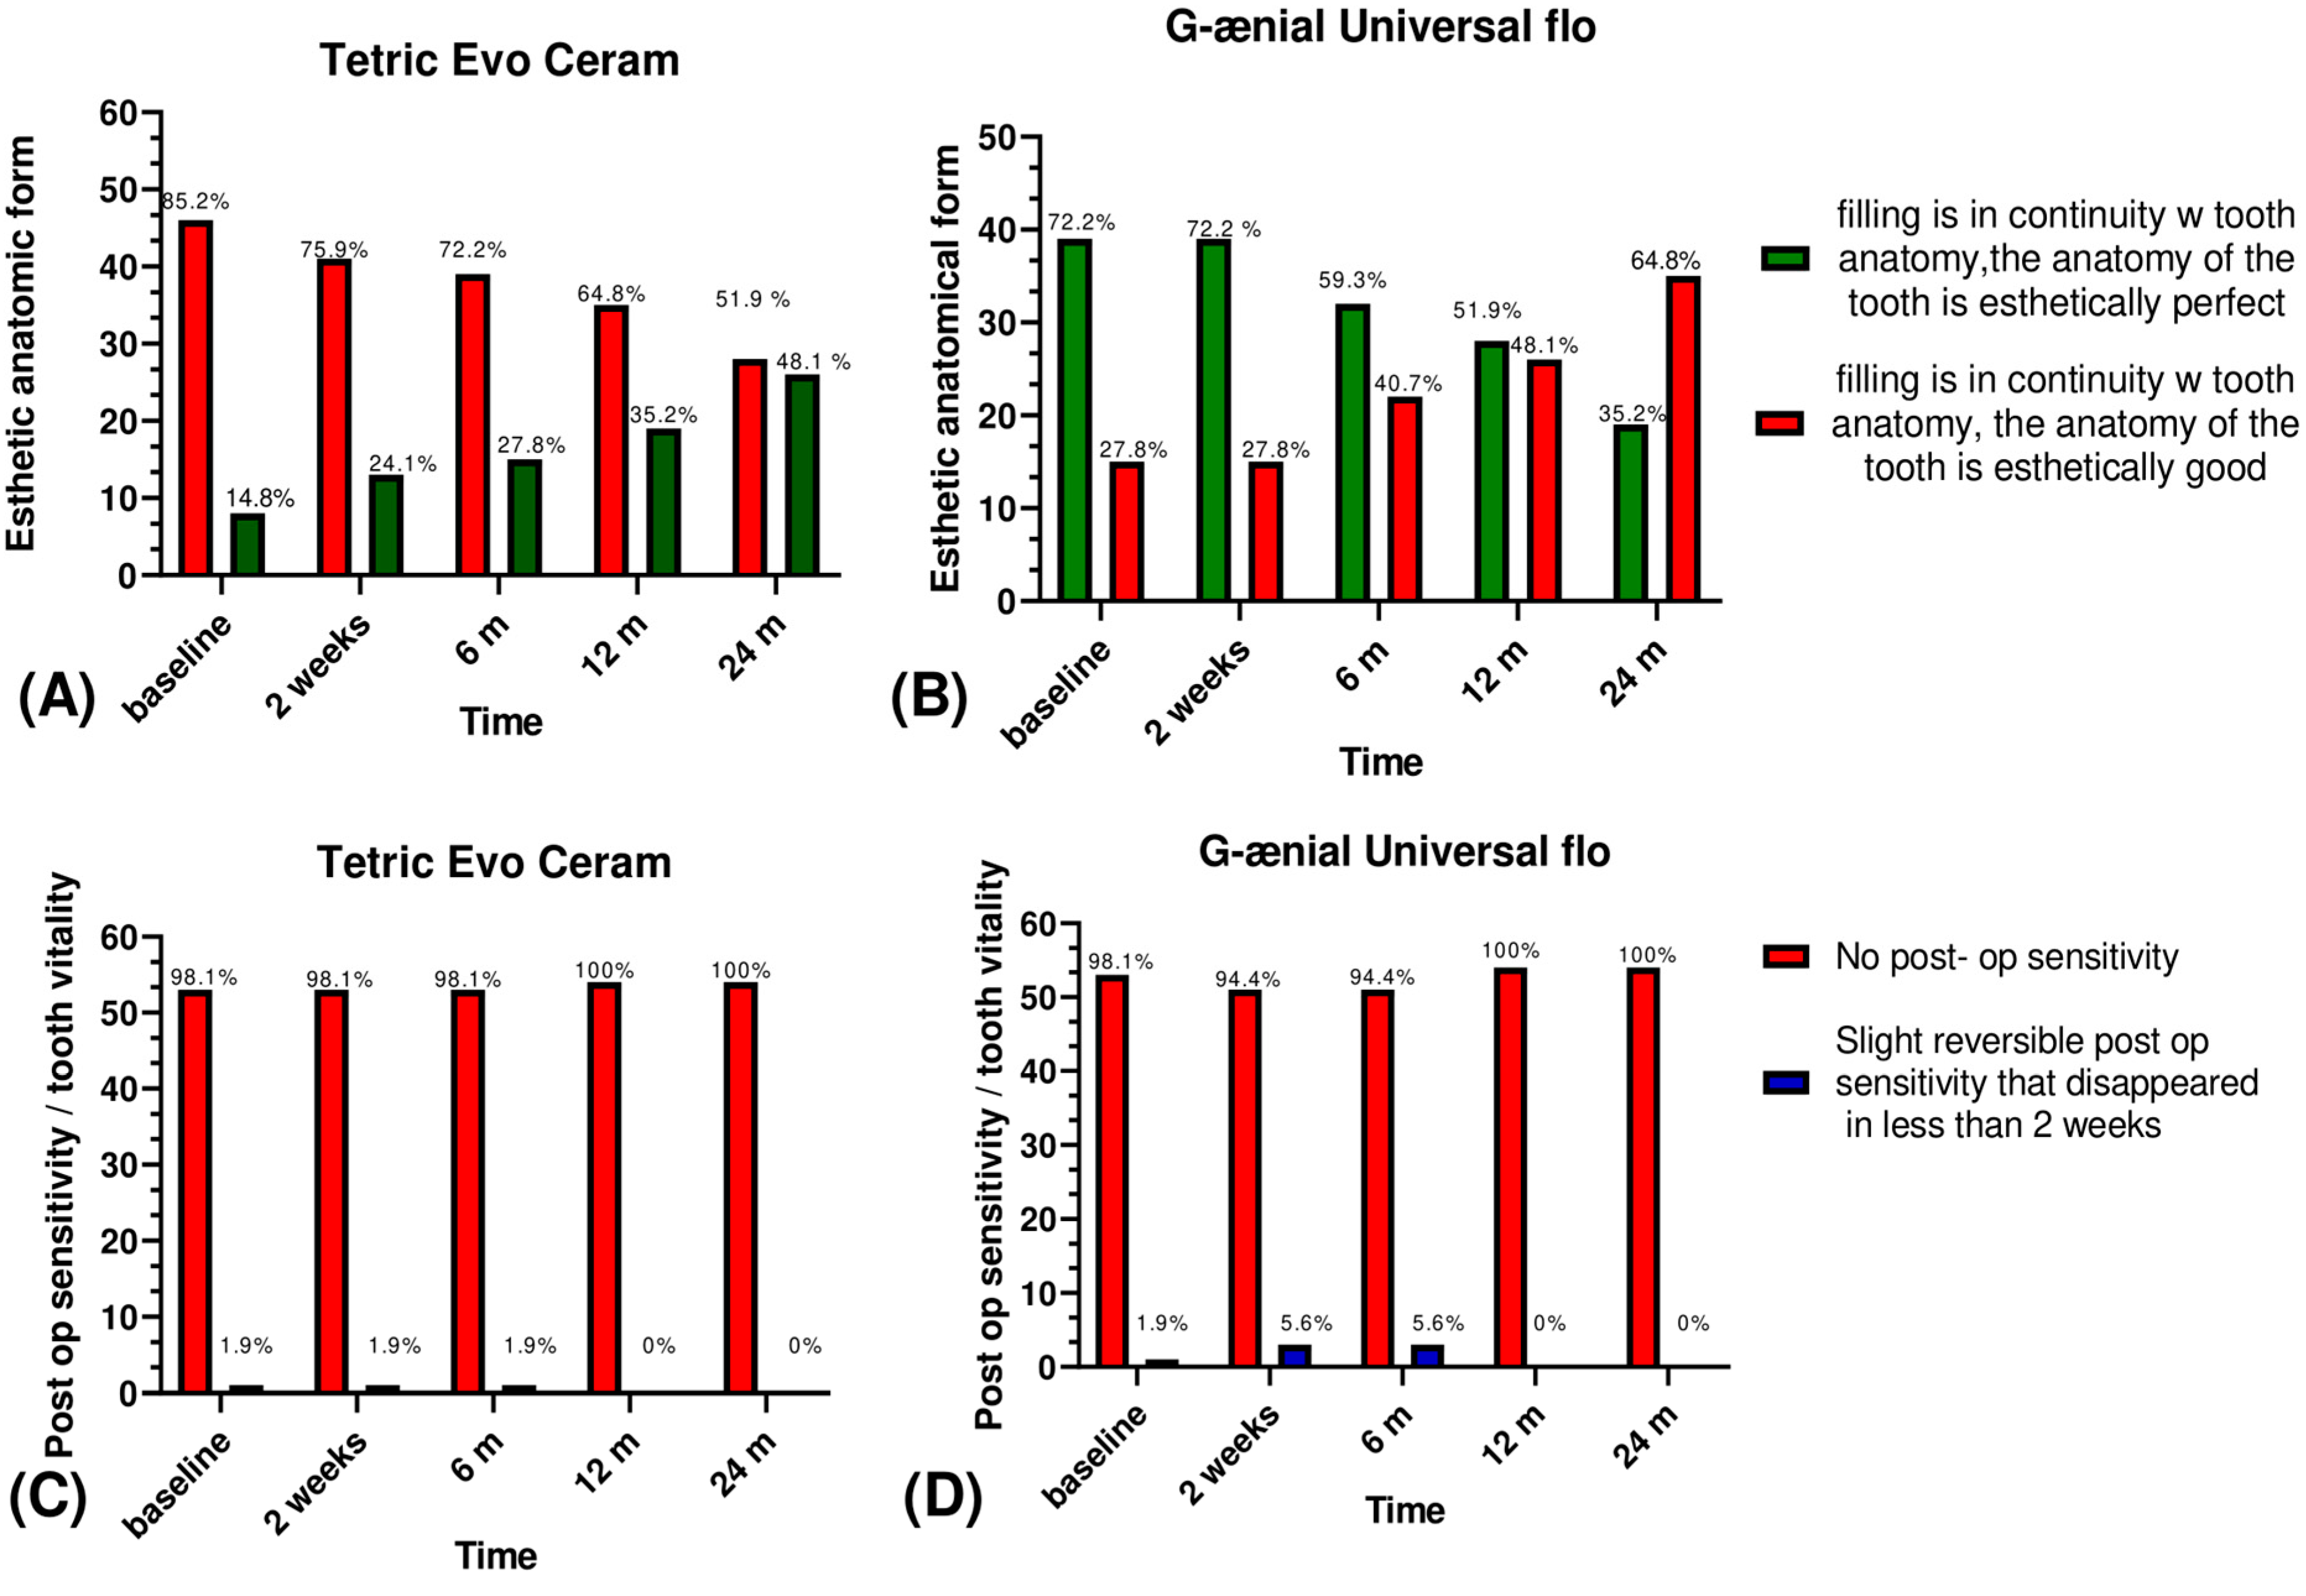

3.1. Esthetic Criteria

3.2. Biological Criteria

| Esthetic anatomical form | The filling is in continuity with tooth anatomy, the anatomy of the tooth is esthetically perfect | The filling is in continuity with tooth anatomy, the anatomy of the tooth is esthetically good | The anatomy of the tooth is not at all esthetic but still clinically acceptable | The anatomy of the tooth is not at all respected | The anatomy of the tooth is completely lost. | ||

| Biological criteria | Postoperative sensitivity and tooth vitality | No post-op sensitivity | Slight reversible post-op sensitivity that disappeared in less than 2 weeks | Slight post-op sensitivity | Severe post-op sensitivity | Severe irreversible post-op sensitivity that led to root canal treatment | |